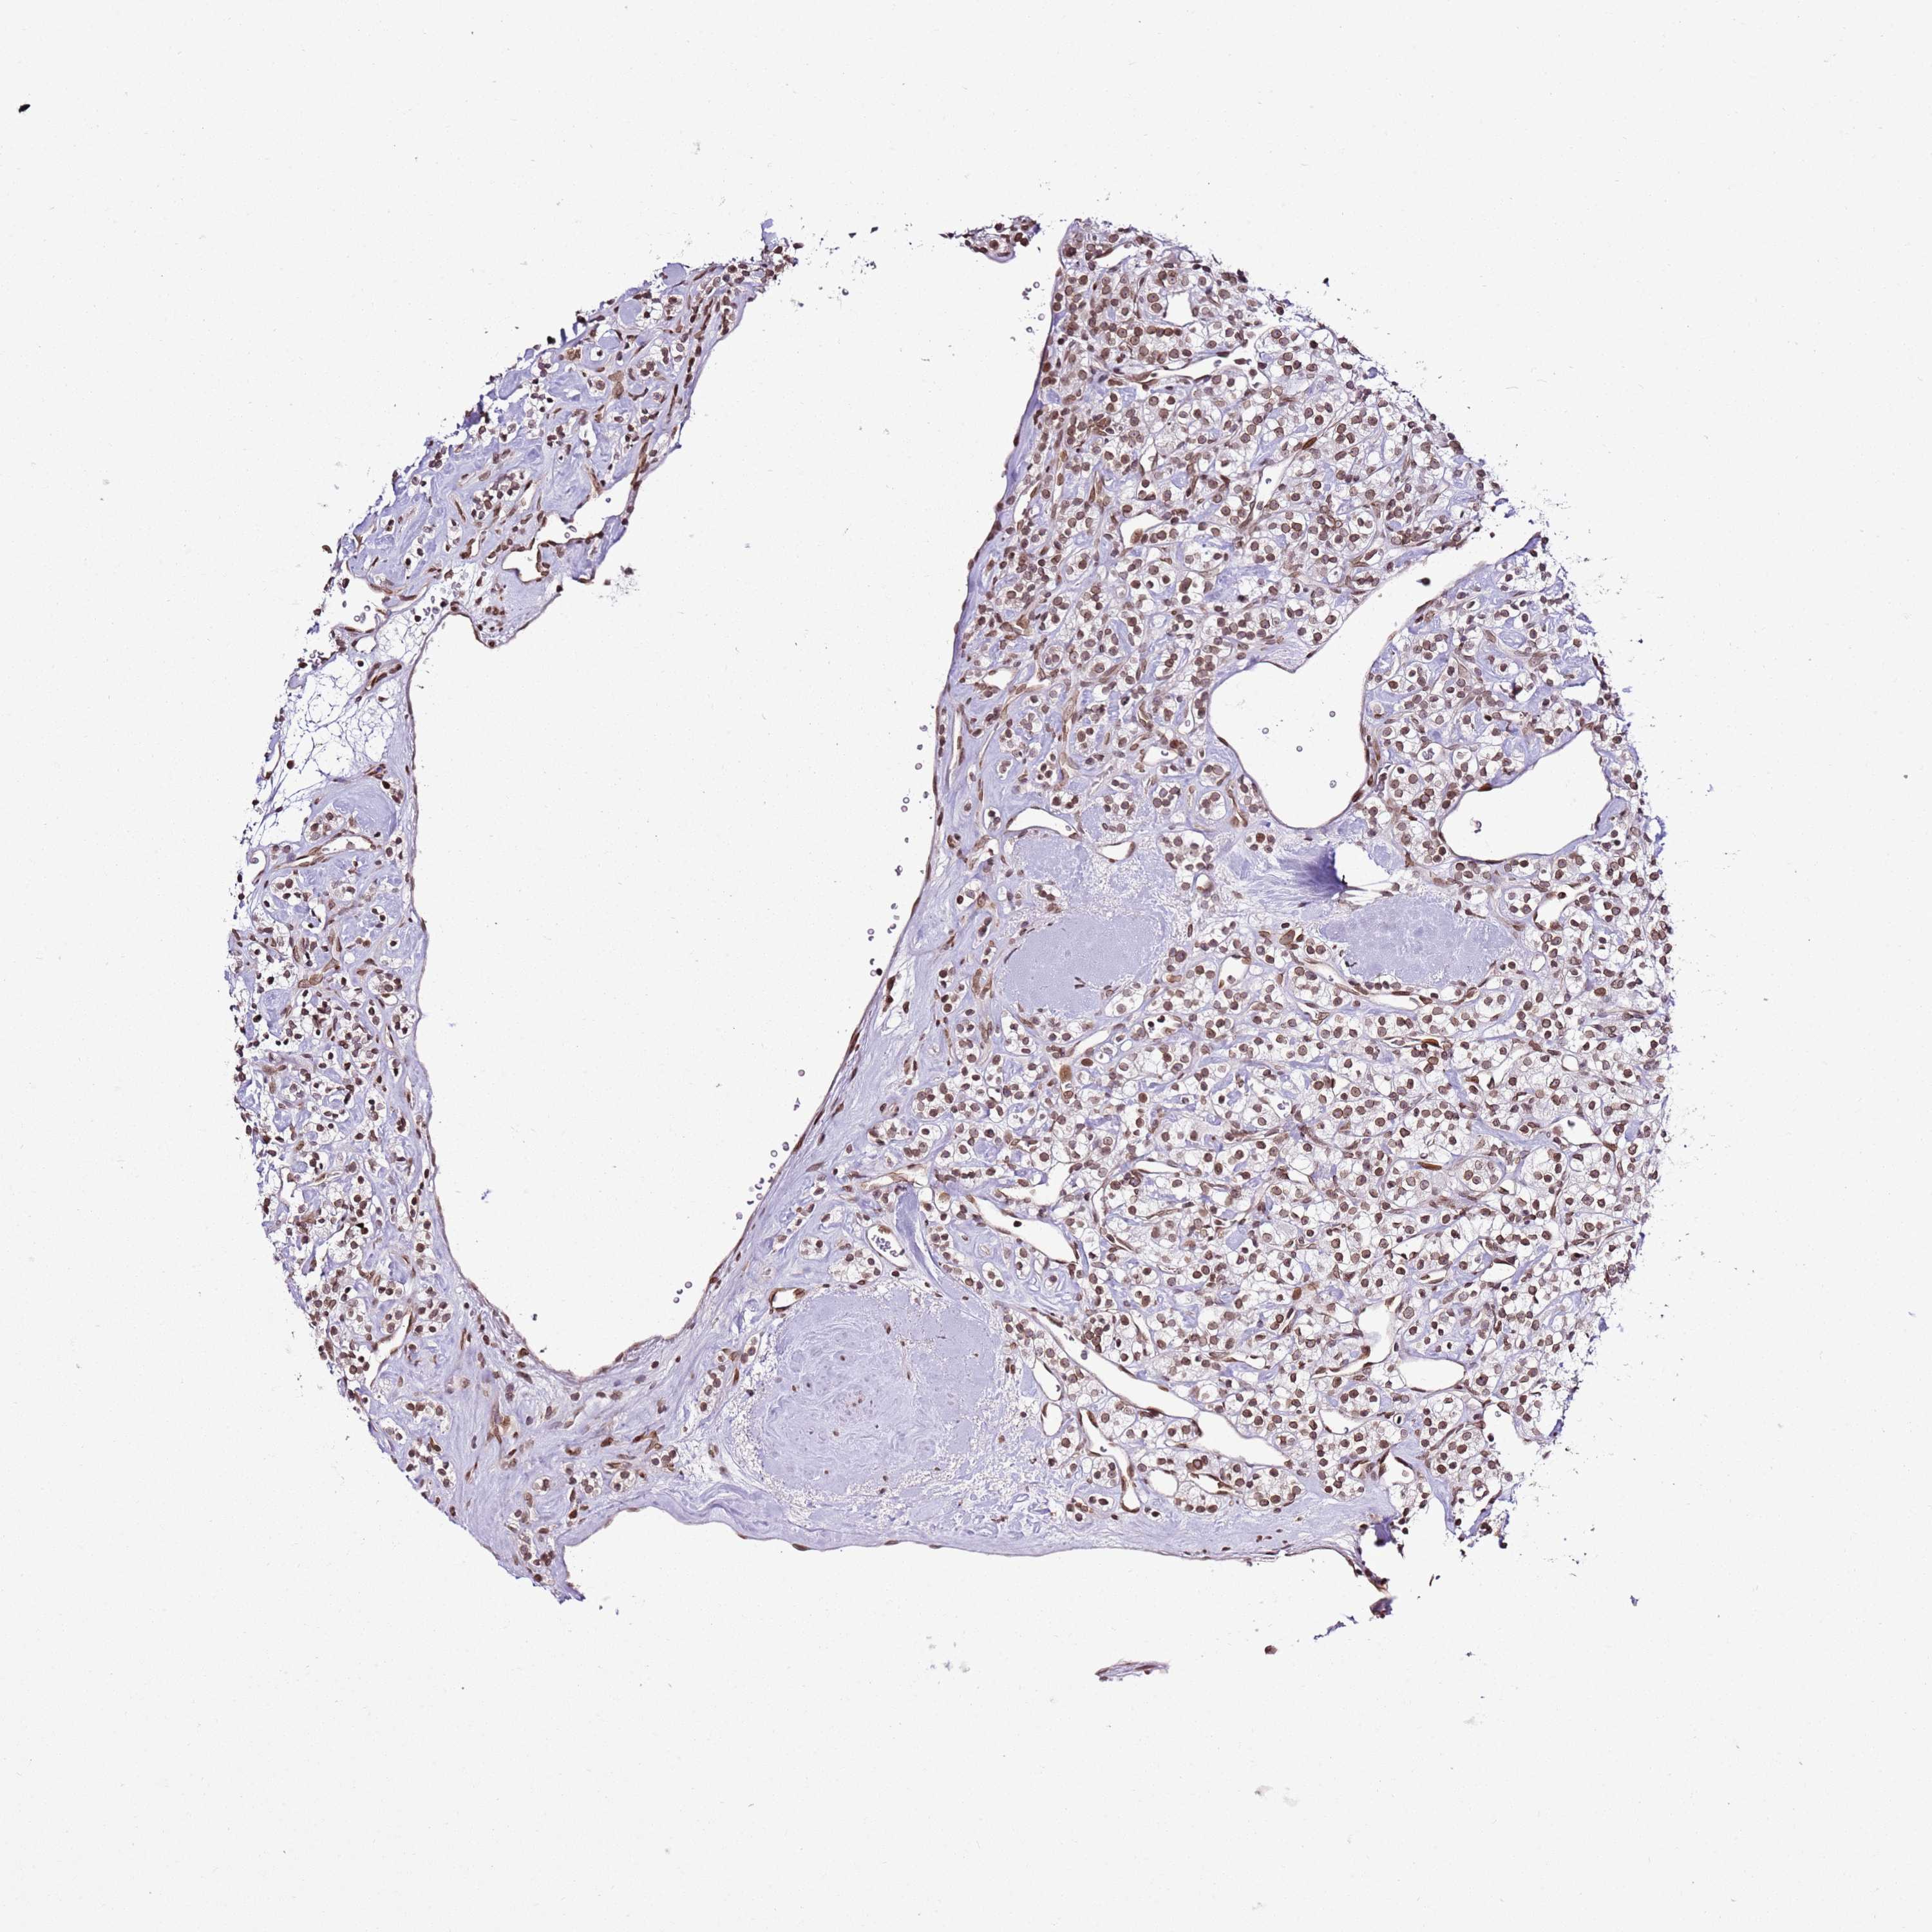

CANCER RENAL CANCER Show tissue menu

KICH TCGA KIRC TCGA KIRC VALIDATION KIRP TCGA PROTEIN RCC CPTAC PROTEIN EXPRESSION

KIDNEY RENAL CLEAR CELL CARCINOMA (VALIDATION) - Interactive survival scatter ploti

POU6F1 is not prognostic in Kidney Renal Clear Cell Carcinoma (validation)